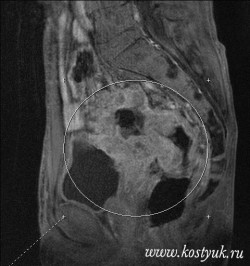

В течение последующих 60 лет много усовершенствований тазовых эвисцераций были внедрены в отношении критериев отбора пациентов, периоперационного лечения, хирургической техники резекционного этапа и технологии реконструктивного этапа. Первичная полная ЭМТ была модифицирована в процедуру, сохраняющую прямую кишку (передняя ЭМТ) или мочевой пузырь (задняя ЭМТ), рисунок 1. До сих пор у ряда пациентов ЭМТ остается единственным вариантом противоопухолевого лечения.

Рис. 1. Передняя (а) и задняя (б) модификации

эвисцерации малого таза